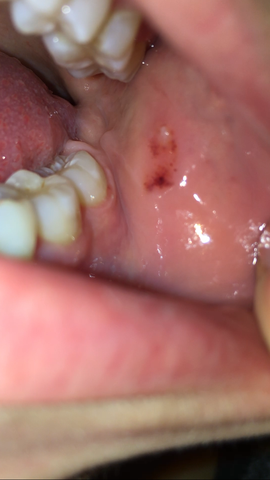

Entzündungen der Mund- und Rachenschleimhaut. Wunde Stellen im Mund. HIV HIV merkt man nicht.

Schleimhautdefekte im Mund und an den Genitalien. Ohne Behandlung durchläuft die HIV-Infektion von der Ansteckung mit HIV bis zum Ausbruch von Aids. Danach bleibt die Infektion oft lange symptomlos obwohl HIV den Körper unbehandelt weiter schädigt.